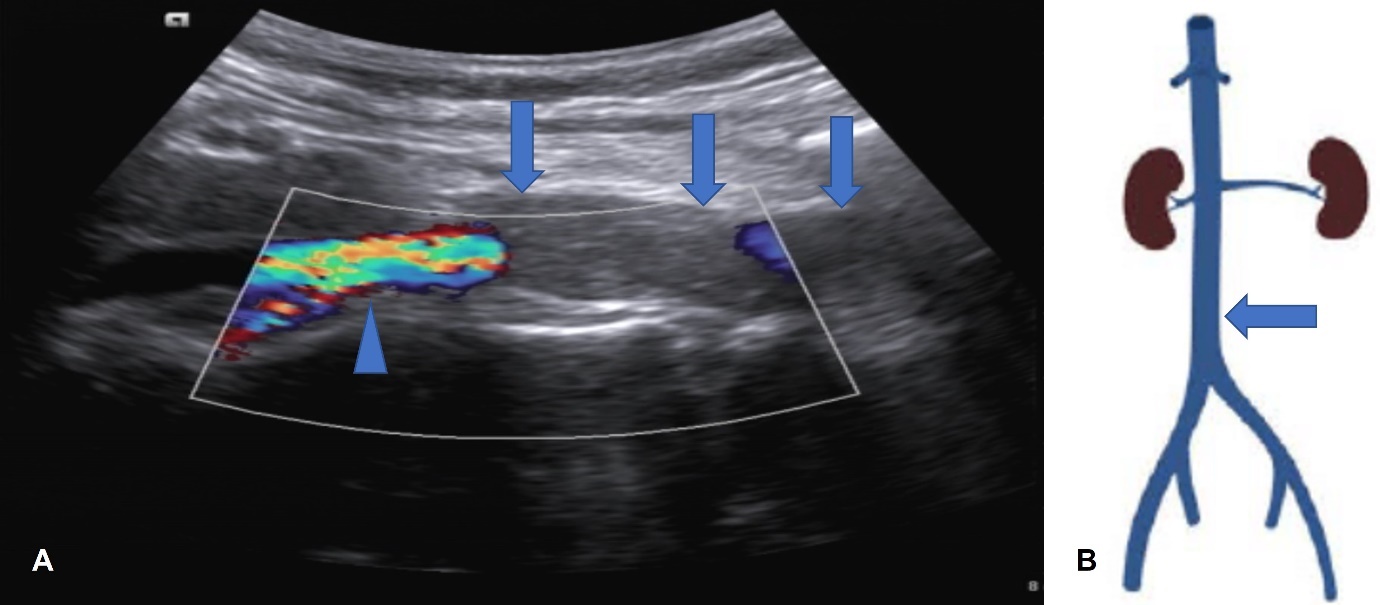

Can thiệp nội mạch điều trị huyết khối tĩnh mạch chủ-chậu phức tạp tại Bệnh viện trường Đại học Y Dược Huế

Vừa qua, Đơn vị Chẩn đoán hình ảnh can thiệp, khoa Chẩn đoán hình ảnh, Bệnh viện trường Đại học Y Dược Huế đã can thiệp thành công một trường hợp...